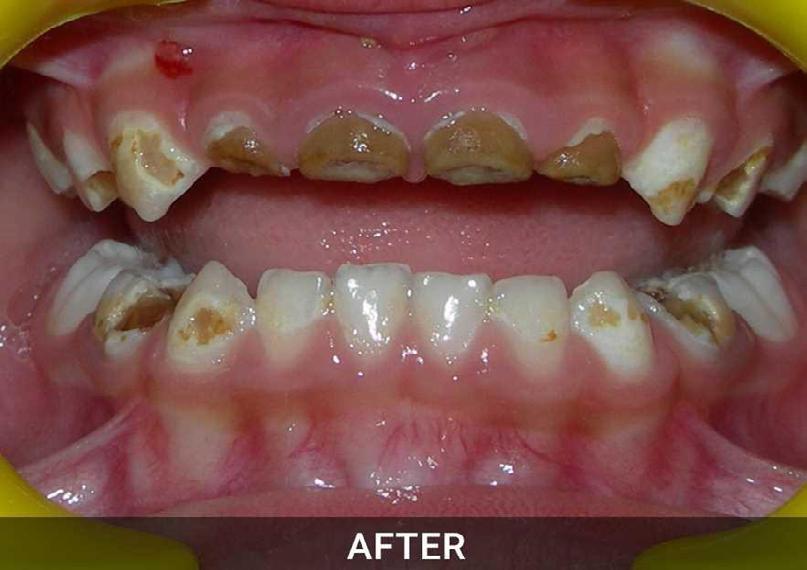

Tερηδόνες θηλασμού (nursing bottle caries)

Στην Ελλάδα για τα παιδιά της προσχολικής ηλικίας, που είναι και η περίοδος που ξεκινά ο τερηδονισμός, σύμφωνα με μελέτη της Ελληνικής οδοντιατρικής ομοσπονδίας σε συνεργασία με την αντίστοιχη παγκόσμια, το 36% των παιδιών μας έχουν ήδη τερηδονικές βλάβες οι οποίες αυξάνονται με την ηλικία.(2)